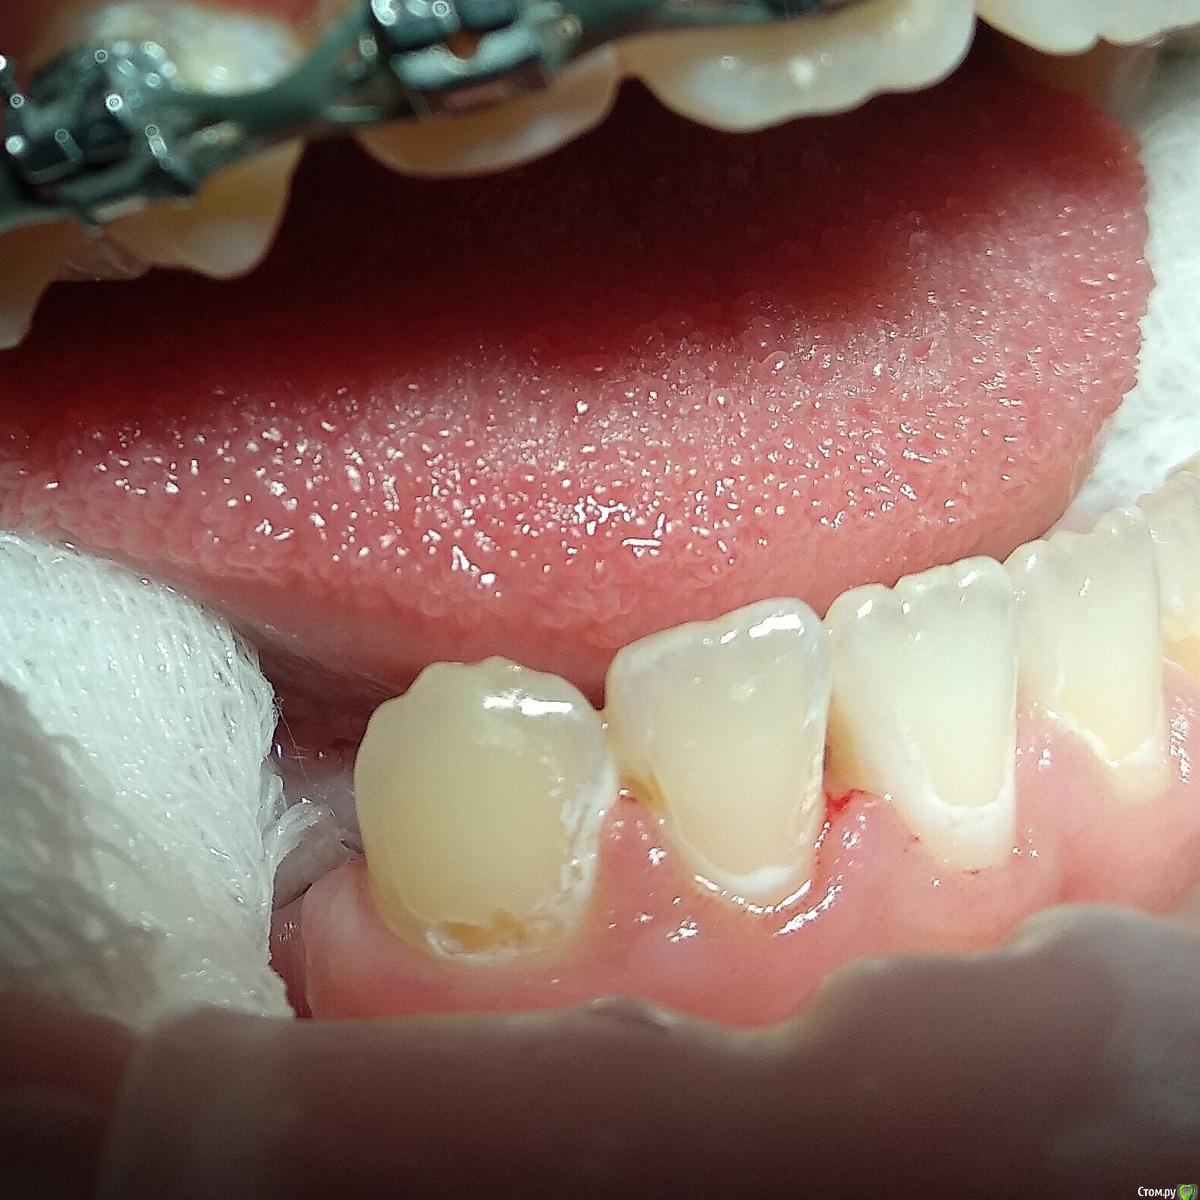

Paganini Опубликовано 13 октября, 2018 Поделиться Опубликовано 13 октября, 2018 (изменено) Приветствую! Помогите помочь пациенту (13 лет). Попросила ортодонта снять брекеты досрочно, потому что с эмалью беда - эмаль скалывается кусками, в местах под брекетами множественные дефекты. При нажатии на эмаль зондом остаются следы. Уверена, что до установки брекетов была уже патология (флюороз или гипоплазия), брекеты всего лишь усугубили ситуацию. С гигиеной тоже все плохо: всегда, когда пациент приходил ко мне на чистку, налета столько, что хоть ложкой снимай... Ставить пломбы? Дефектов очень много, и я думаю, что держаться это будет плохо, эмаль хрупкая. Сейчас комплексно укрепляем эмаль.P.S.: я не детский врач. Я гигиенист и терапевт с небольшим опытом работы. Изменено 13 октября, 2018 пользователем Paganini Ссылка на комментарий

Paganini Опубликовано 13 октября, 2018 Автор Поделиться Опубликовано 13 октября, 2018 Пострадали почти все резцы и клыки, жевательная группа в порядке, но там мало что есть (первичная адентия). Ссылка на комментарий